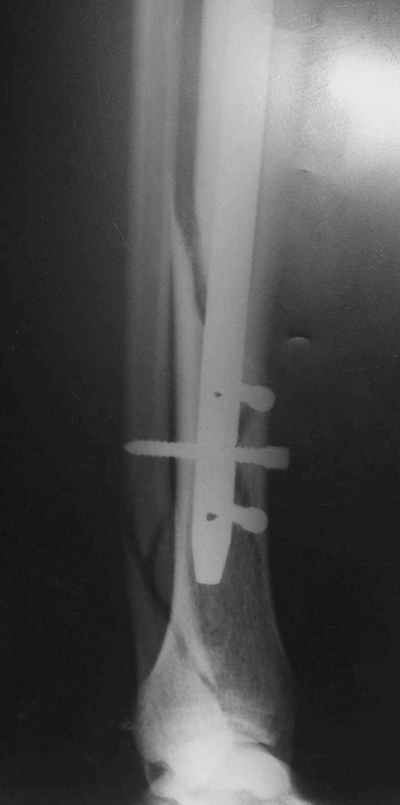

Re: Потекли блокирующие винты, после интрамедулярн

Рентгенограмы